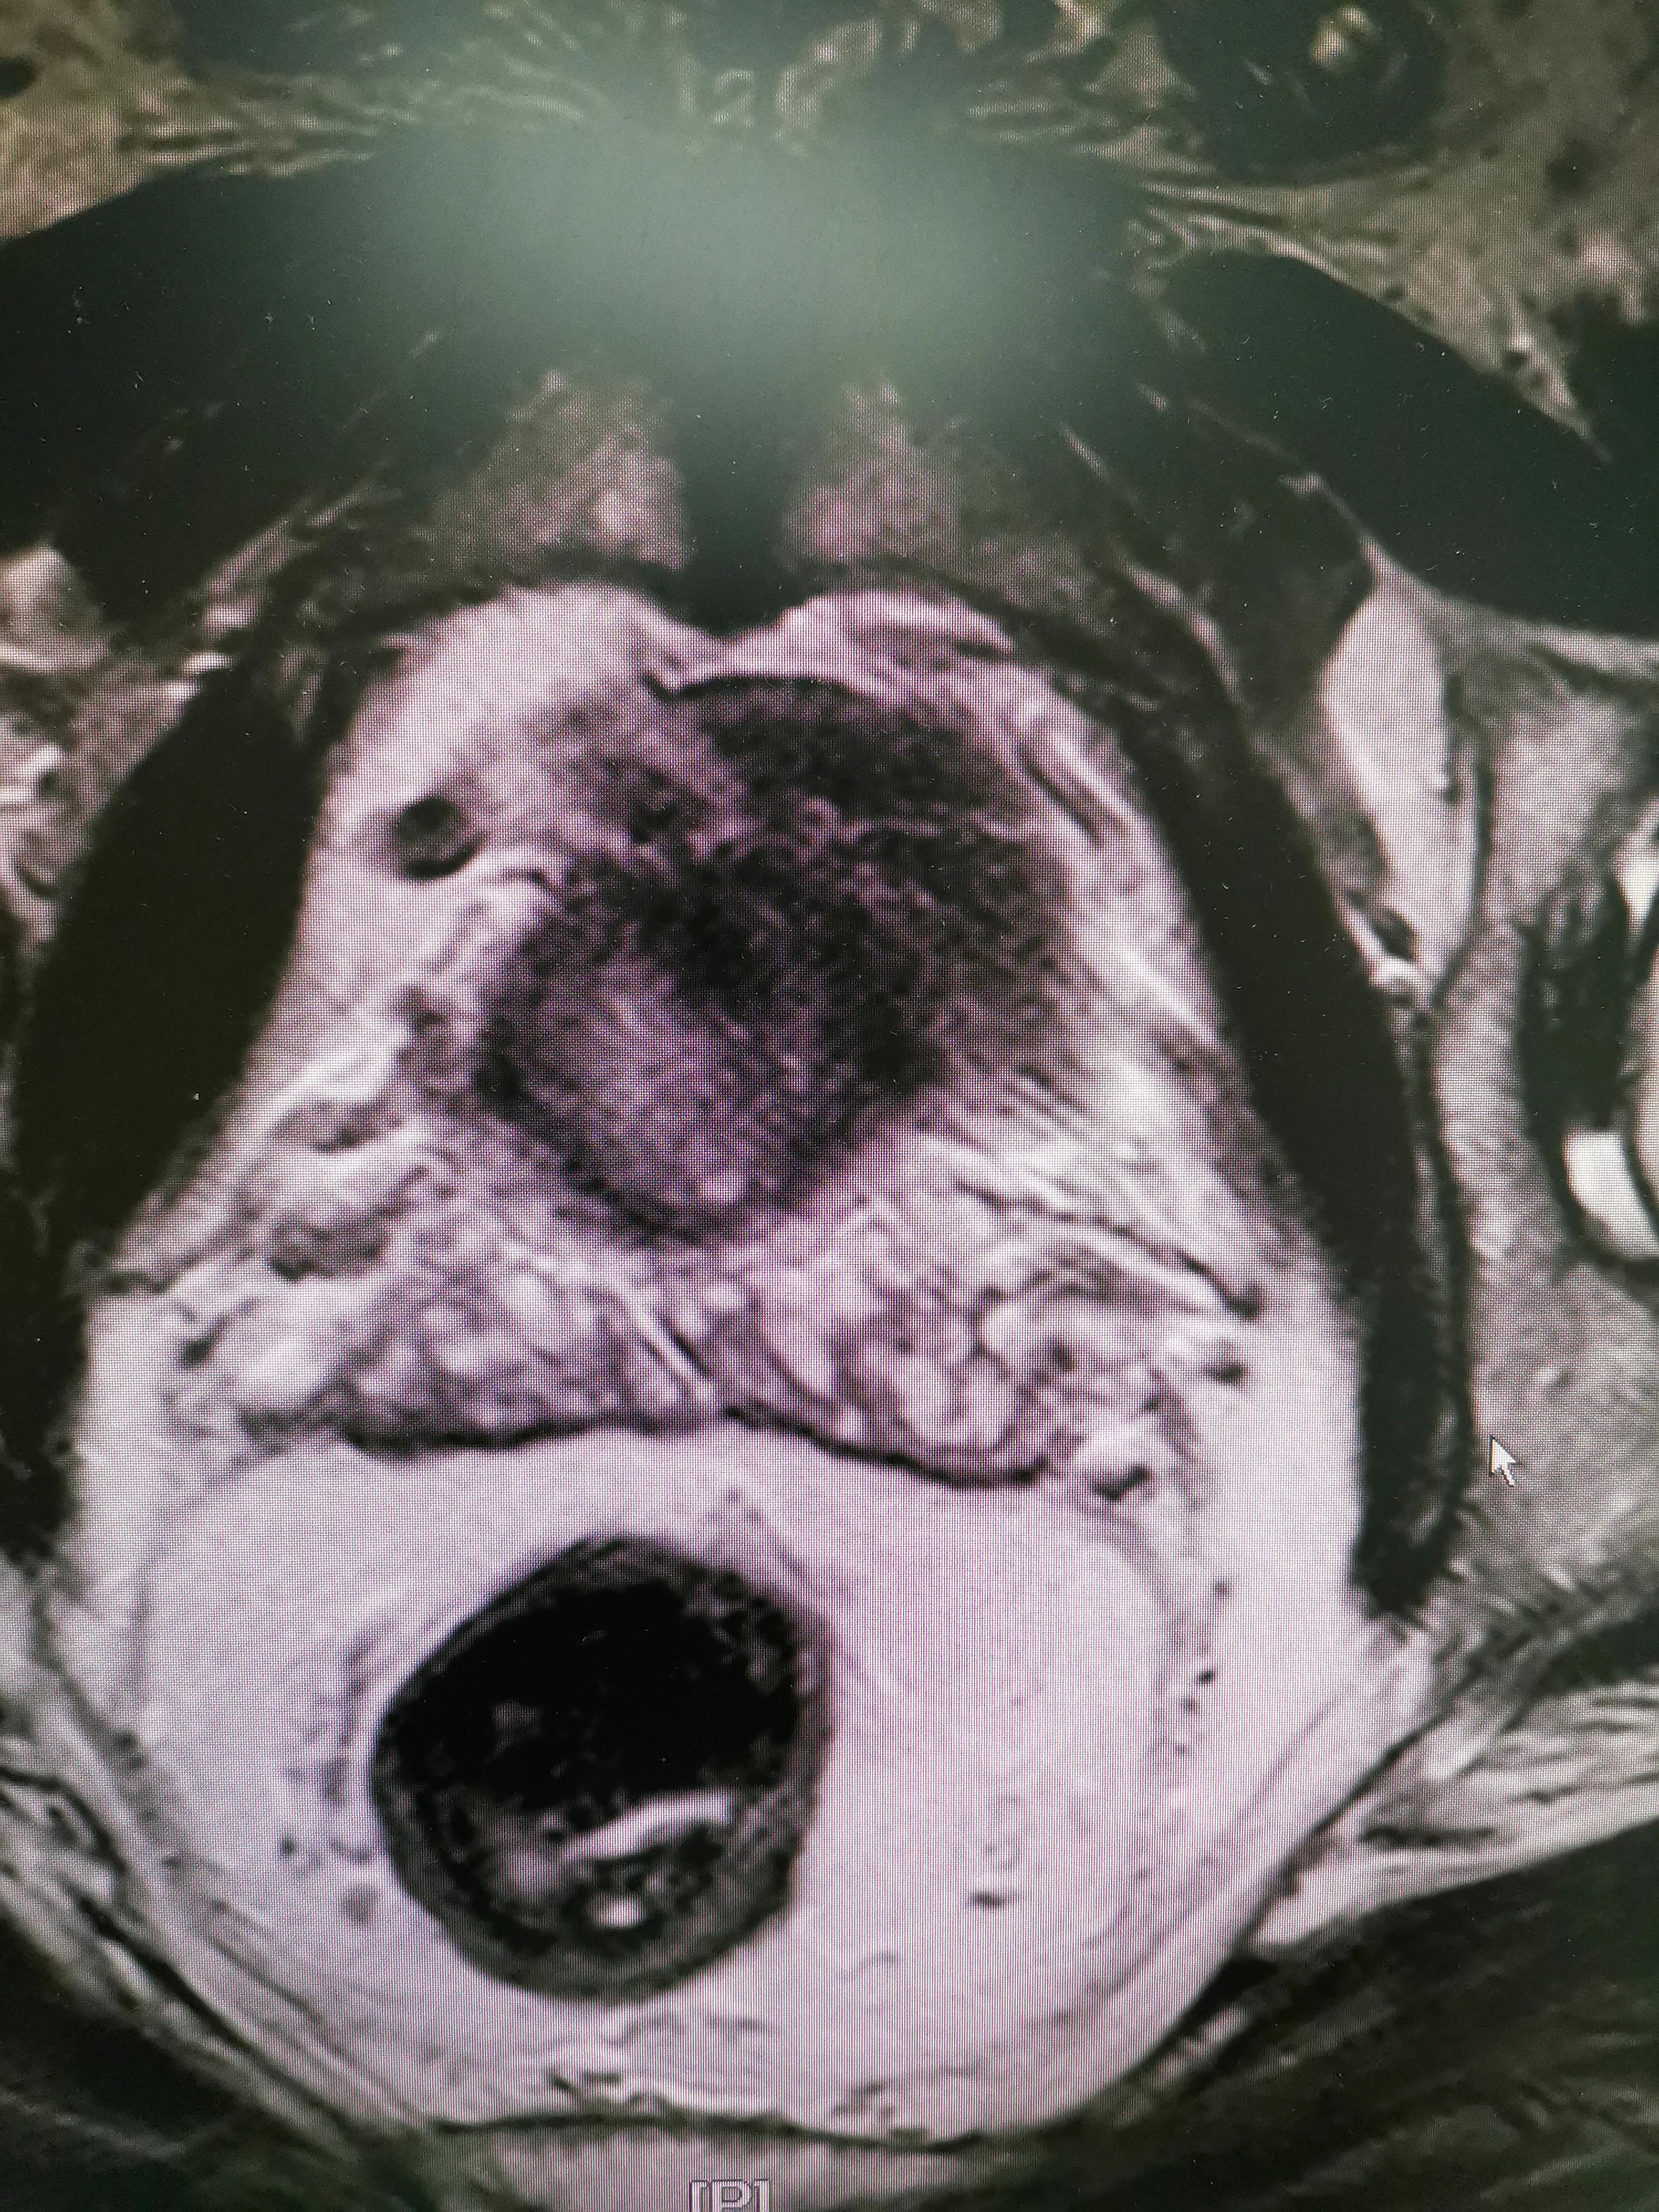

5、УЗИ (цветная допплерография)

С помощью цветной ультрасонографии предстательной железы (особенно трансректального УЗИ предстательной железы) можно точно определить размер и структуру простаты, наличие воспалительных изменений, а также выявить наличие опухолевых узлов, кальцинатов и т.д.